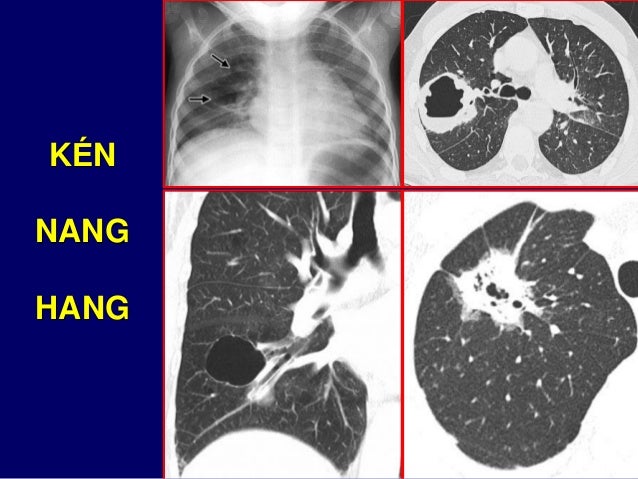

20. 20. CỬA SỔ PHẾ CHỦ

21. 21. RỐN PHỔI

43. 43. KÉN NANG HANG

44. 44. NANG DƯỚI RỐN PHỔI TRÁI